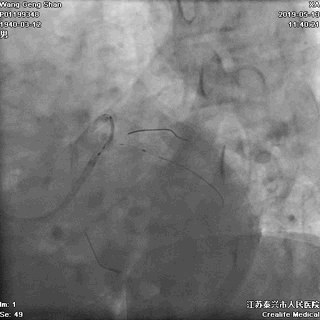

05 LM-LAD支架植入

右头位定位

蜘蛛位定位

LCX球囊拘禁,主支支架释放

回撤LCX球囊